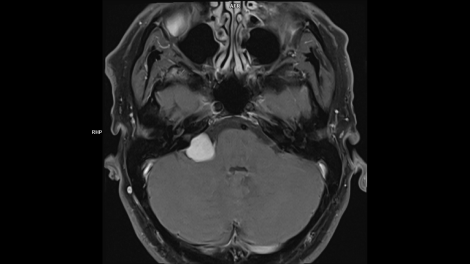

Whether it is head, neck, spine, abdomen or MSK – our clinical experts have complete confidence in the ability of MAGNETOM Free.Max to deliver excellent diagnostic quality for all these standard clinical MRI applications.